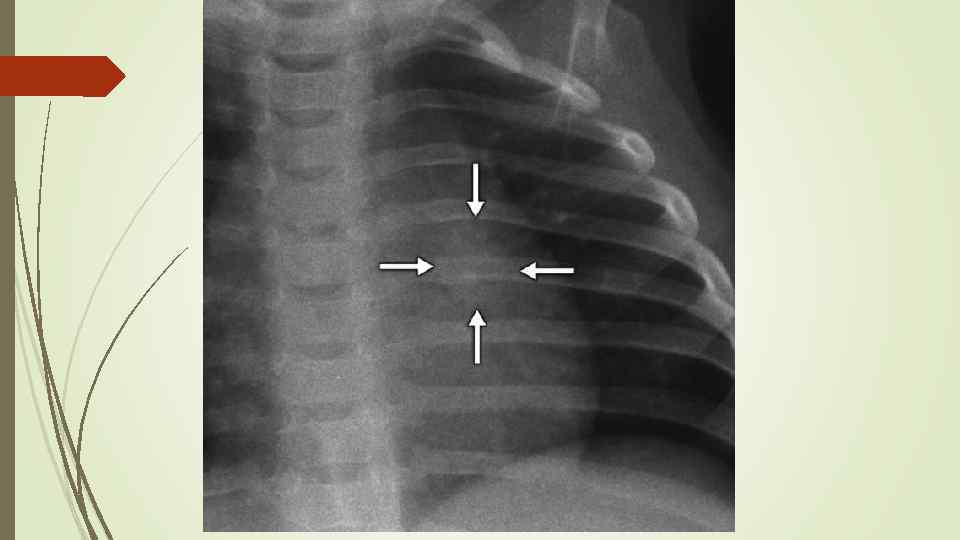

Бронхопневмония Характерно наличие двухсторонних множественных очаговых теней. Контуры очагов нечеткие, интенсивность тени небольшая. Инфильтрация неоднородна. Мелкие, малоинтенсивные очаги не всегда выявляются на снимках. Легочный рисунок усилен на всем протяжении легких. Корни расширены, не структурны. Как правило, отмечается реакция плевры, могут быть и экссудативные плевриты.

Бронхопневмония Характерно наличие двухсторонних множественных очаговых теней. Контуры очагов нечеткие, интенсивность тени небольшая. Инфильтрация неоднородна. Мелкие, малоинтенсивные очаги не всегда выявляются на снимках. Легочный рисунок усилен на всем протяжении легких. Корни расширены, не структурны. Как правило, отмечается реакция плевры, могут быть и экссудативные плевриты.

bronhopneumoni

bronhopneumoni